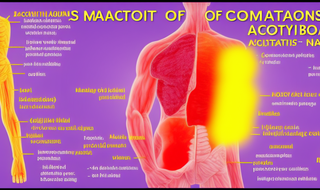

支气管炎是一种使支气管通道发炎并导致咳嗽的疾病。要止咳,可以尝试以下方法:

1. 保持室内空气湿润:使用加湿器或在房间内放置水盆等可以增加空气湿度的工具,有助于缓解咳嗽症状。

2. 多喝水:保持足够的水分摄入,有助于稀释痰液,缓解喉咙干燥和刺痛感。

3. 避免刺激性物质:减少接触烟草烟雾、空气污染、粉尘和化学物质等刺激性物质,以减少咳嗽的发作。

4. 休息充足:适当休息可以帮助身体恢复,减少咳嗽症状。

5. 热敷:用热水袋或热毛巾敷在胸部和背部,有助于舒缓支气管,减轻咳嗽症状。

6. 合理饮食:避免食用刺激性食物和油腻食物,多摄入富含维生素C和抗炎食物的饮食,有助于增强免疫力,帮助康复。

7. 医生建议:如果咳嗽持续严重或伴有其他症状,如胸闷、气促、发热等,建议及时就诊医生,遵循医生的指导进行治疗。